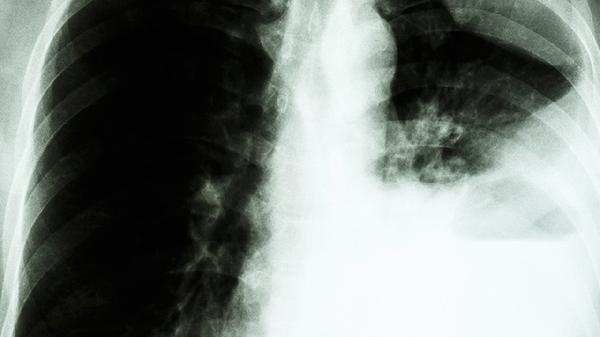

肺部毛玻璃样结节是怎么回事

肺部毛玻璃样结节可能由炎症、感染、肺出血、肺水肿、早期肺癌等原因引起,可通过抗感染治疗、手术切除、定期随访等方式处理。

部分毛玻璃样结节为早期肺腺癌表现,尤其持续存在的纯毛玻璃结节或混合性结节。这类结节可能增长缓慢,但需高度警惕。诊断依赖病理活检,治疗以手术切除为主,如肺段切除术。术后需长期随访排除复发。